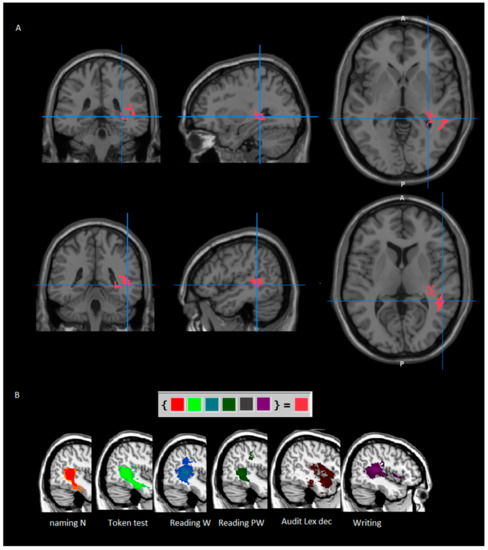

image